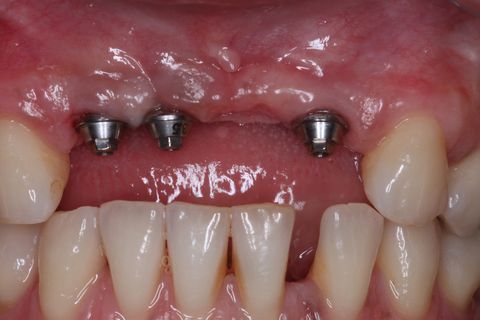

Implantes Neodent Instalados

Instalação de parafusos de proteção com 2mm de comprimento

Sutura final

Minipilares instalados. Nota-se apenas 3 minipilares pois um dos implantes foi perdido. Instalamos um novo implante que também foi perdido. Optamos em manter apenas 3 implantes e finalizar a prótese fixa parafusada.

Paciente do sexo feminino, 32 anos e 10 mêses de idade, com ausência dos incisivos centrais e laterais superiores, associado a um defeito ósseo vestibular côncavo. Realizamos planejamento reverso, ou seja, enceramento diganóstico prévio para avaliação do defeito ósseo em termos de quantidade e do posicionamento final das próteses. A paciente foi submetido a um enxerto ósseo autógeno do ramo ascendente lado direito e fixação dos blocos ósseos na área receptora, com fixação dos mesmos através de parafusos de fixação com cabeça expandida Neodent. Após 6 meses foram instalados 4 implantes Neodent.